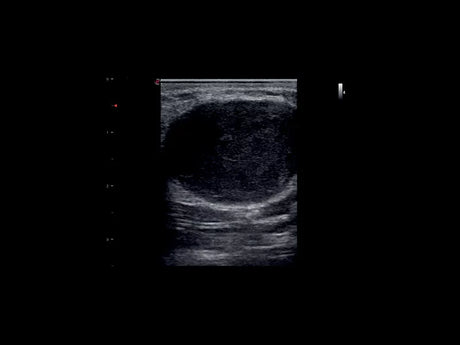

Les échographes Esaote offrent une restitution d’image d’une grande précision, permettant un diagnostic fiable dans toutes les spécialités. Le traitement numérique optimise le contraste et la netteté, réduisant les artefacts et améliorant la détection des tissus pathologiques. Ces performances sont particulièrement appréciées en gynécologie, où la lisibilité des structures pelviennes ou obstétricales est déterminante.

Un gynécologue privilégiera un échographe offrant une résolution d’image très fine et une compatibilité avec des sondes endocavitaires. Un kinésithérapeute ou un médecin du sport recherchera plutôt un appareil portable, léger et rapide à mettre en route. Les praticiens généralistes apprécieront la polyvalence et la facilité d’entretien, tandis que les vétérinaires auront besoin d’un système robuste et facilement transportable.